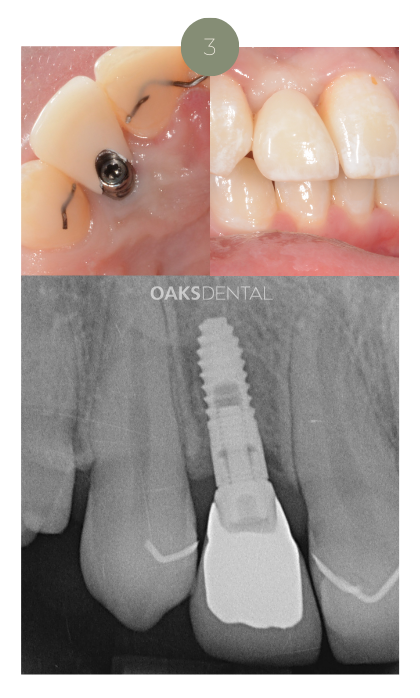

4. Final Restoration

Once healed, a custom-made ceramic crown, bridge, or denture is attached.

This final restoration is shaped and coloured to match your existing teeth for a seamless result.